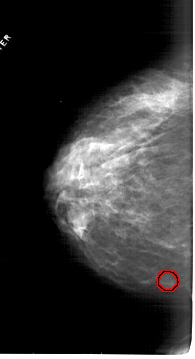

A_1814_1.RIGHT_CC

RIGHT_CC LINES 6316 PIXELS_PER_LINE 3811 BITS_PER_PIXEL 12 RESOLUTION 43.5 NON_OVERLAY

FILE: A_1814_1.LEFT_CC.OVERLAY

TOTAL_ABNORMALITIES 1

ABNORMALITY 1

LESION_TYPE MASS SHAPE OVAL MARGINS CIRCUMSCRIBED

ASSESSMENT 3

SUBTLETY 3

PATHOLOGY BENIGN

TOTAL_OUTLINES 1